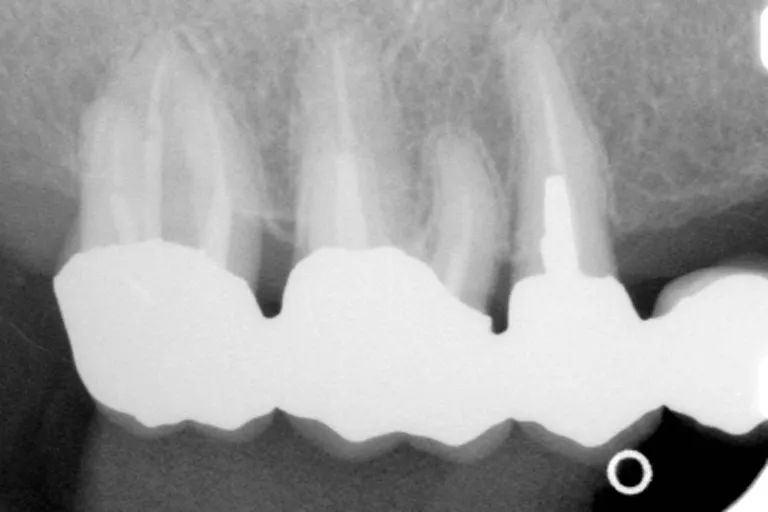

■術前・他医院で治療された被せもので精度が低く歯との境の縁があっていないため段差ができています

■術 前■

被せ物の縁が

あっていない

■術前・被せものはセメントを盛って取付け段差を埋めますが縁の制度が低いと境目のセメントが取れた時に大きな段差ができます

■保険対応の被せ物

保険で指定された金パラジウム合金(主成分は50%近くは銀)を使います。目で見ながらの作業で、縁の合わせ方は、良くて100ミクロン(10分の1ミリ)です。セメントして付けると、150ミクロンくらい縁が合っていません。この程度の精度では、短期間では問題ありませんが、虫歯にかかりやすい人では、縁からセメントが溶けて、2次的な虫歯が発生することが多く起こります。

レントゲンで、縁が歯と合っていない被せ物では、このレベルの何倍も不適合であることは珍しくありません。被せものの縁に爪が引っかかるレベルでは、歯の寿命に影響がある場合も出てきます。当クリニックでは、自費において、さらにレベルの高い治療ができており、保険の対応においても、十分な配慮が行われています。当クリニックの被せ物は保険であっても、爪が引っかかる、レントゲンでズレがあるということはありません。